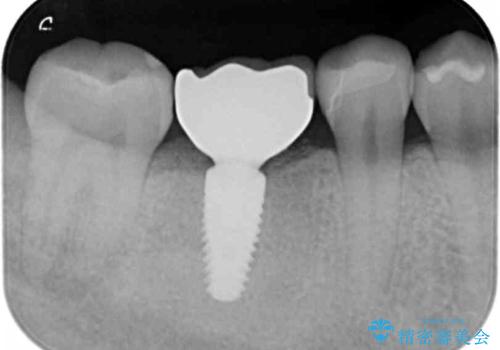

抜歯後は、前後の歯を削らずにしっかりと咬合力を回復できるインプラント治療を選択されました。

- 44万円(ストローマンインプラント・チタンカスタムアバットメント・仮歯・ジルコニアクラウン)費用は治療当時の料金となります

虫歯の放置により吸収してしまった骨も造成を行うことでインプラント周囲環境をしっかりと整えています。